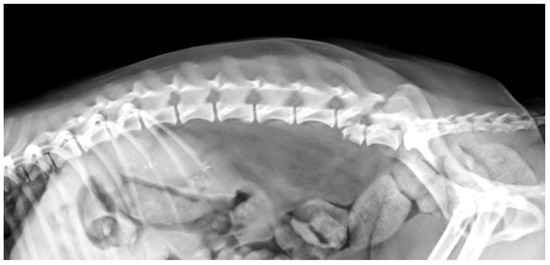

2.1. Imaging Protocols

3.2. Diagnostic Imaging